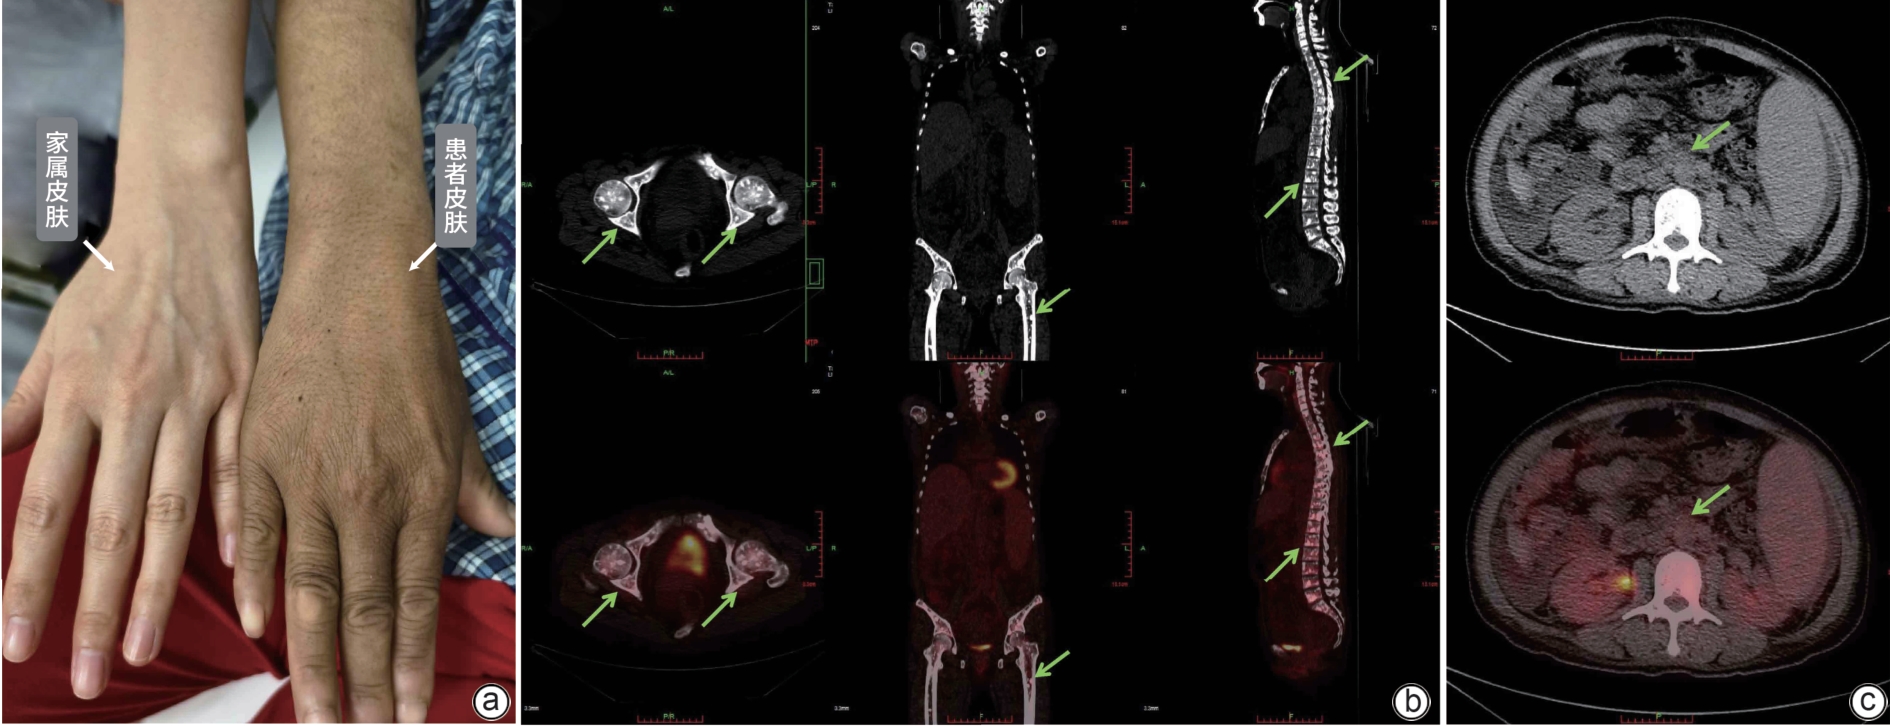

POEMS syndrome with hepatosplenomegaly as the initial manifestation: A report of two cases

Ye ZHANG, Wenqing WANG, Jing LI, Qianrong BAI, Jiayu LI, Yan CHENG, Miaomiao FANG, Nana GAO, Changxing HUANG

2025, 41(1): 127-132. DOI: 10.12449/JCH250119

Abstract(956) HTML (253) PDF (2190KB)(81)

Abstract:

POEMS syndrome is a rare condition associated with plasma cell disorders, and it often involves multiple systems and has diverse clinical manifestations. This article reports two cases of POEMS syndrome with hepatosplenomegaly as the initial manifestation. During the course of the disease, the patients presented with lower limb weakness, hepatosplenomegaly, lymph node enlargement, ascites, hypothyroidism, positive M protein, and skin hyperpigmentation, and 18F-FDG PET-CT imaging revealed bone lesions mainly characterized by osteolytic changes and plasma cell tumors. There was an increase in the serum level of vascular endothelial growth factor. The patients were finally diagnosed with POEMS syndrome, and the symptoms were relieved after immunomodulatory treatment.